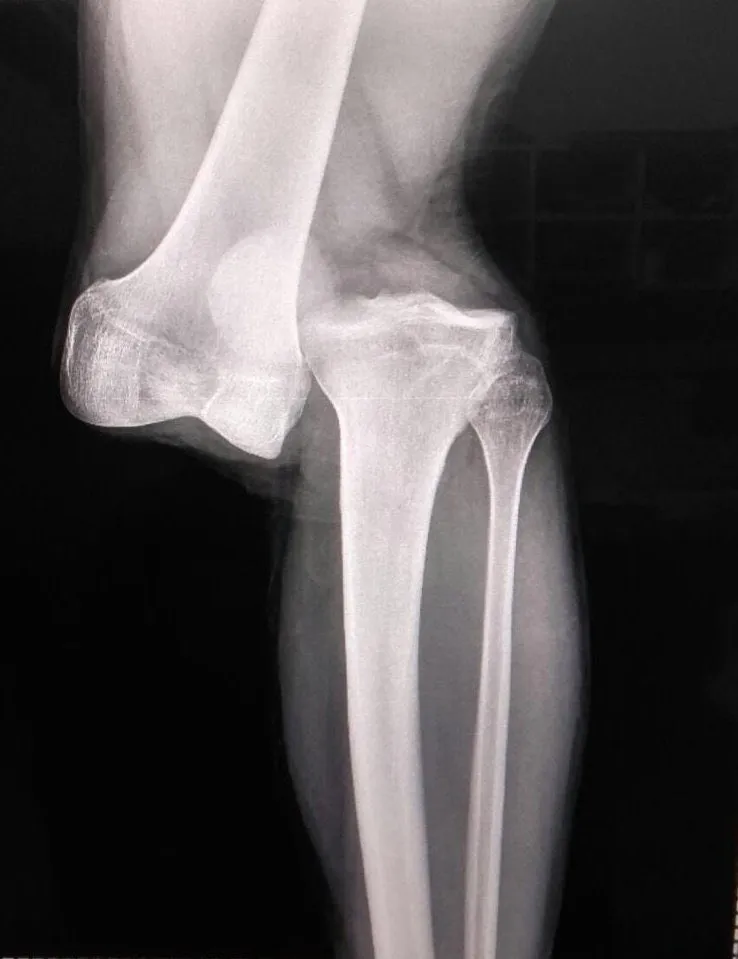

Con el correr de las horas además salió a la luz la radiografía de Sánchez que grafica perfectamente lo destrozada que quedó su pierna izquierda tras la fuerte entrada: Es casi completa la separación del fémur y el peroné.

“En 23 años cómo médico nunca vi una lesión así, Villani (doctor de la AFA) en 40 años me dijo lo mismo. Es casi una separación del fémur y el peroné. Hay rotura de cruzado anterior, posterior y hay que ver cómo están lo meniscos”, afirmó Alejandro Ronconi, médico de Argentinos Juniors.

La radiografía de la grave lesión de Luciano Sánchez. | Foto: Archivo.

En ese sentido, Ronconi declaró que “hay que hacer una reconstrucción. La recuperación es de entre 10 y 12 meses. Se necesitarán dos etapas quirúrgicas. Destaco la entereza de Luciano, ya que una vez le inmovilizaron la zona se dedicó a calmar a su novia y a todos los que lo rodeaban en ese momento de desesperación explicando que ya no le dolía”.